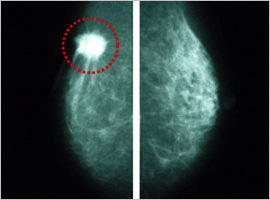

マンモグラフィ専用装置

赤枠内の白い部分が乳がん腫瘤

乳がんに伴う石灰化